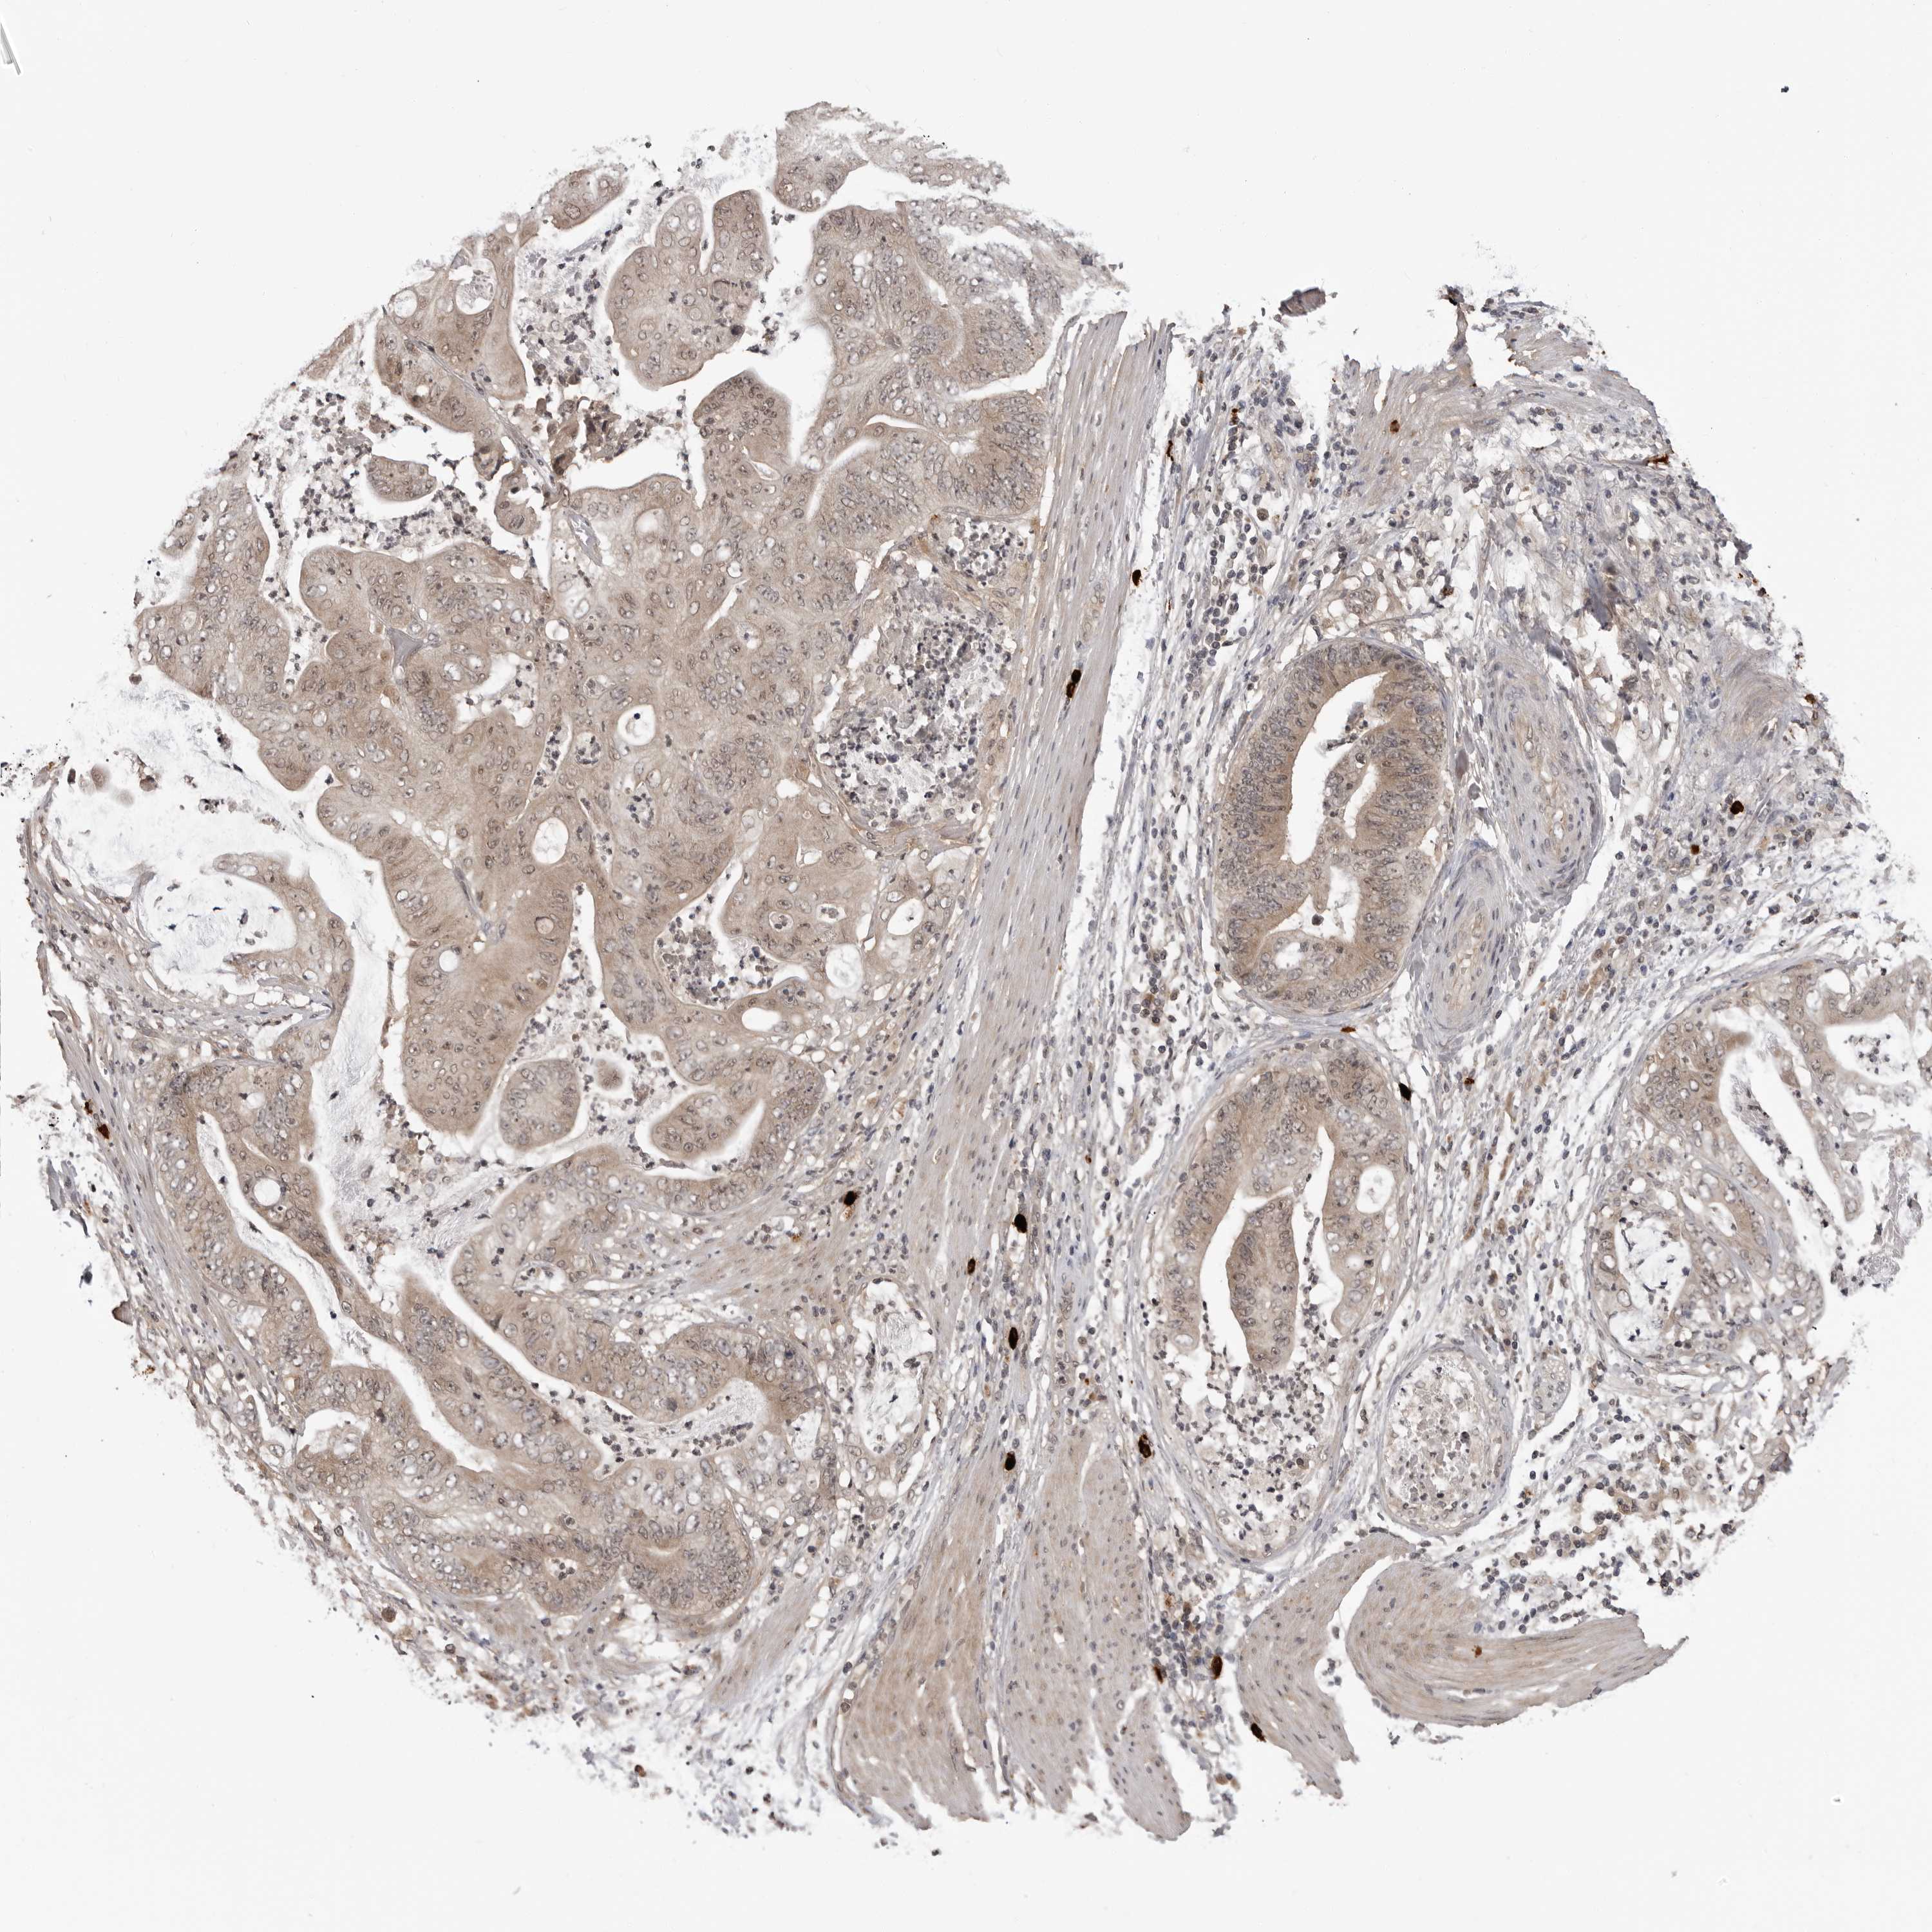

STOMACH CANCER - Protein expressioni

A mouse-over function shows sample information and annotation data. Click on an image to view it in a full screen mode. Samples can be filtered based on level of antibody staining by selecting one or several of the following categories: high, medium, low and not detected. The assay and annotation is described here.

Note that samples used for immunohistochemistry by the Human Protein Atlas do not correspond to samples in the TCGA dataset.

Antibody stainingi

Antibody staining in the annotated cell types in the current human tissue is reported as not detected, low, medium, or high, based on conventional immunohistochemistry profiling in selected tissues. This score is based on the combination of the staining intensity and fraction of stained cells.

Each image is clickable and will lead to virtual microscopy that enables deeper exploration of all samples and also displays staining intensity scores, fraction scores and subcellular localization as well as patient and tissue information for each sample.

Antibody CAB025972

Staining

High

Medium

Low

Not detected

Intensity

Strong

Moderate

Weak

Negative

Quantity

>75%

75%-25%

<25%

None

Location

Nuclear

Cytoplasmic/membranous

Cytoplasmic/membranous,nuclear

Adenocarcinoma, NOS